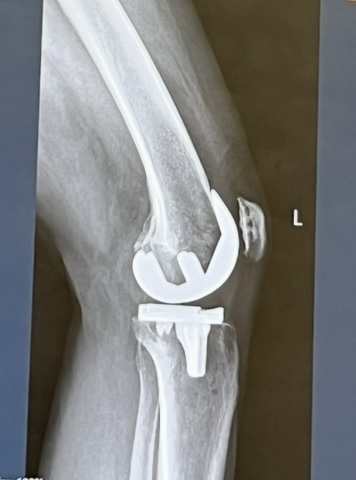

š Happy Belated Birthday, Knees! š

My knees are about one- and one-half years old and boy has life changed since the last time I wrote.Ā I wanted to start off with a quote from my last post:

Would you believe me if I said that physical sensation of pain is a distant memory?Ā I can clearly remember the emotional suffering, but the body memory of pain is gone.Ā I donāt even remember what itās like to have to climb and descend the stairs one let at a time, clinging on to the railing for dear life, or to feel the instability due to the grinding of bone on bone with even the slightest movement. I have my life back in a very profound way.Ā I can do things now that I havenāt been able to do in many years.Ā Things that we take for grantedā¦.like bending over, standing for more than a few minutes, getting in and out of a car.Ā And the bigger things like doing a full squat with weights, or one legged deadlift, swim, ride a bike, walk several miles (or 90, but Iāll save that for another post), or run up and down stairs (very carefully).

I had my surgery just after turning 64. That year was about healing and tempering expectations. But when I hit 65, I realized I didnāt have to just survive, I could thrive. Iāll be sharing some of those adventures in the next posts, because 65 can be pretty darn fabulous.